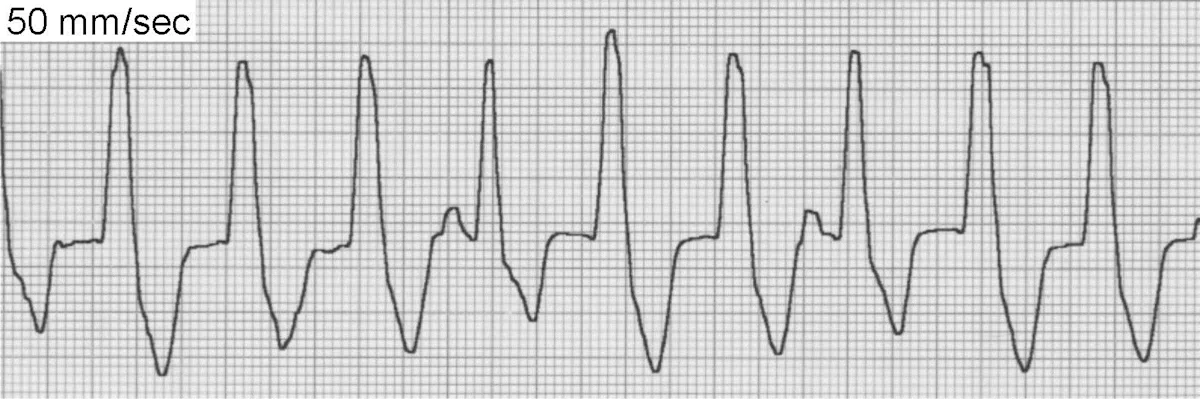

AF (Figure 1) is the classic irregularly irregular, fast cardiac rhythm produced by disorganized and chaotic depolarization of atrial myocardial tissue, resulting in the inability to produce effective atrial contractions. AF is one of the most important arrhythmias in dogs but is uncommon in cats. Most cases are secondary to severe atrial enlargement and underlying heart disease.

The 3 ECG hallmarks of AF include absence of identifiable P waves in all leads, supraventricular QRS complexes, and an irregularly irregular rhythm. The baseline may frequently display oscillations but the organization is ill defined.